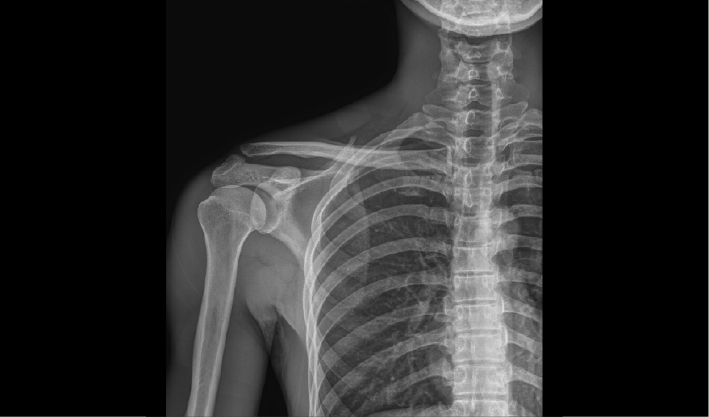

一板多位,灵活应用

无线平板可自由移动摆,方便担架位、轮椅位等

特殊体位患者拍摄。

常规DR摄影检查,如:胸片位,腹部位,四肢位等。